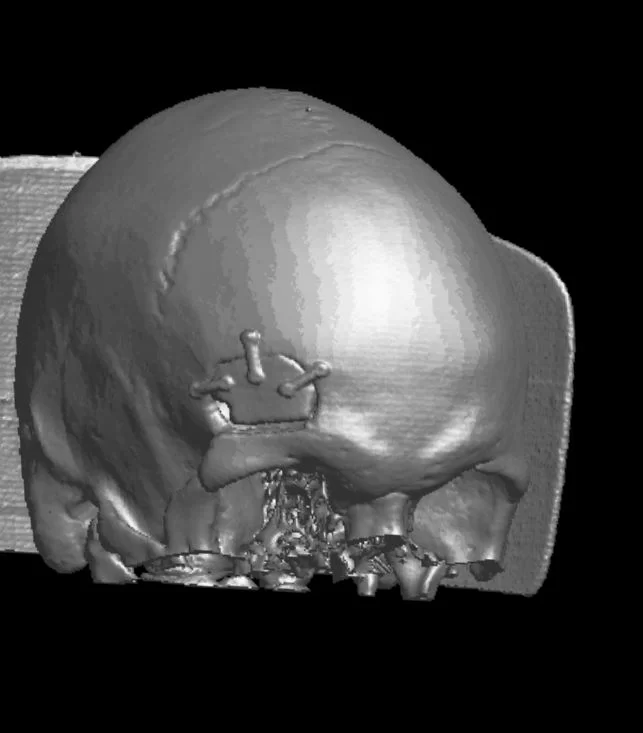

Διενεργήθη δεξιά υπερκόγχιος κρανιοτομία (τομή στο φρύδι) και ολική εξαίρεση της βλάβης.

Οι ελάχιστα επεμβατικές τεχνικές (όπως για παράδειγμα η κρανιοτομία δίκην κλειδαρότρυπας) προσφέρουν πολλά πλεονεκτήματα σε σχέση με τις κλασσικές μεθόδους και άριστο αισθητικό αποτέλεσμα.